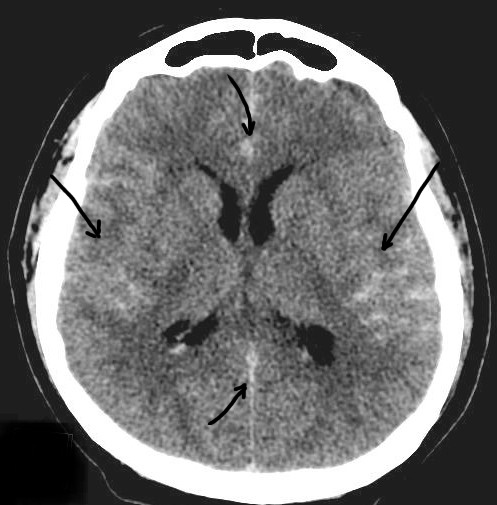

Вариант субарахноидального кровоизлияния: кровь (светлая, яркая) расположена по конвексу мозга, в корковых бороздах, межполушарной щели спереди и сзади, а также базальных цистернах мозга